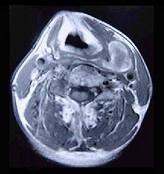

问题 男性,40岁,发现左侧颈部小包块,CT、MRI检查如图所示,请选择最可能的诊断()

选项 A.神经鞘瘤 B.神经纤维瘤 C.海绵状血管瘤 D.肿大淋巴结 E.副神经节瘤

答案 C